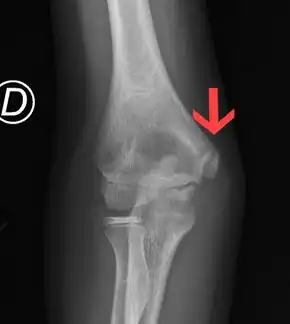

Commonly involved sports include baseball pitchers, tennis, and volleyball.[2] The underlying mechanism involves excessive stress at the growth plate at the medial epicondyle.[4] Diagnosis is generally based on symptoms.[5] Thought; often normal, X-rays occasionally show slight widening or an avulsion fracture.[4][3] Once growth plates have closed ulnar collateral ligament injury of the elbow more commonly occurs.[6][3]

.jpg)

Diagnosis is generally based on physical exam and history, as X-rays are typically normal. Often there is repetitive, high volume, overhand throwing. There may be tenderness, swelling, limited extension, and stiffness of the elbow on exam.[12] X-rays may be helpful to check if the growth plate is open, see if loose bone chips are present, and see if there are signs of early arthritis.[10] X-rays can also rule out other elbow issues, such as fractures of the medial epicondyle from a trauma.[12][9][10]